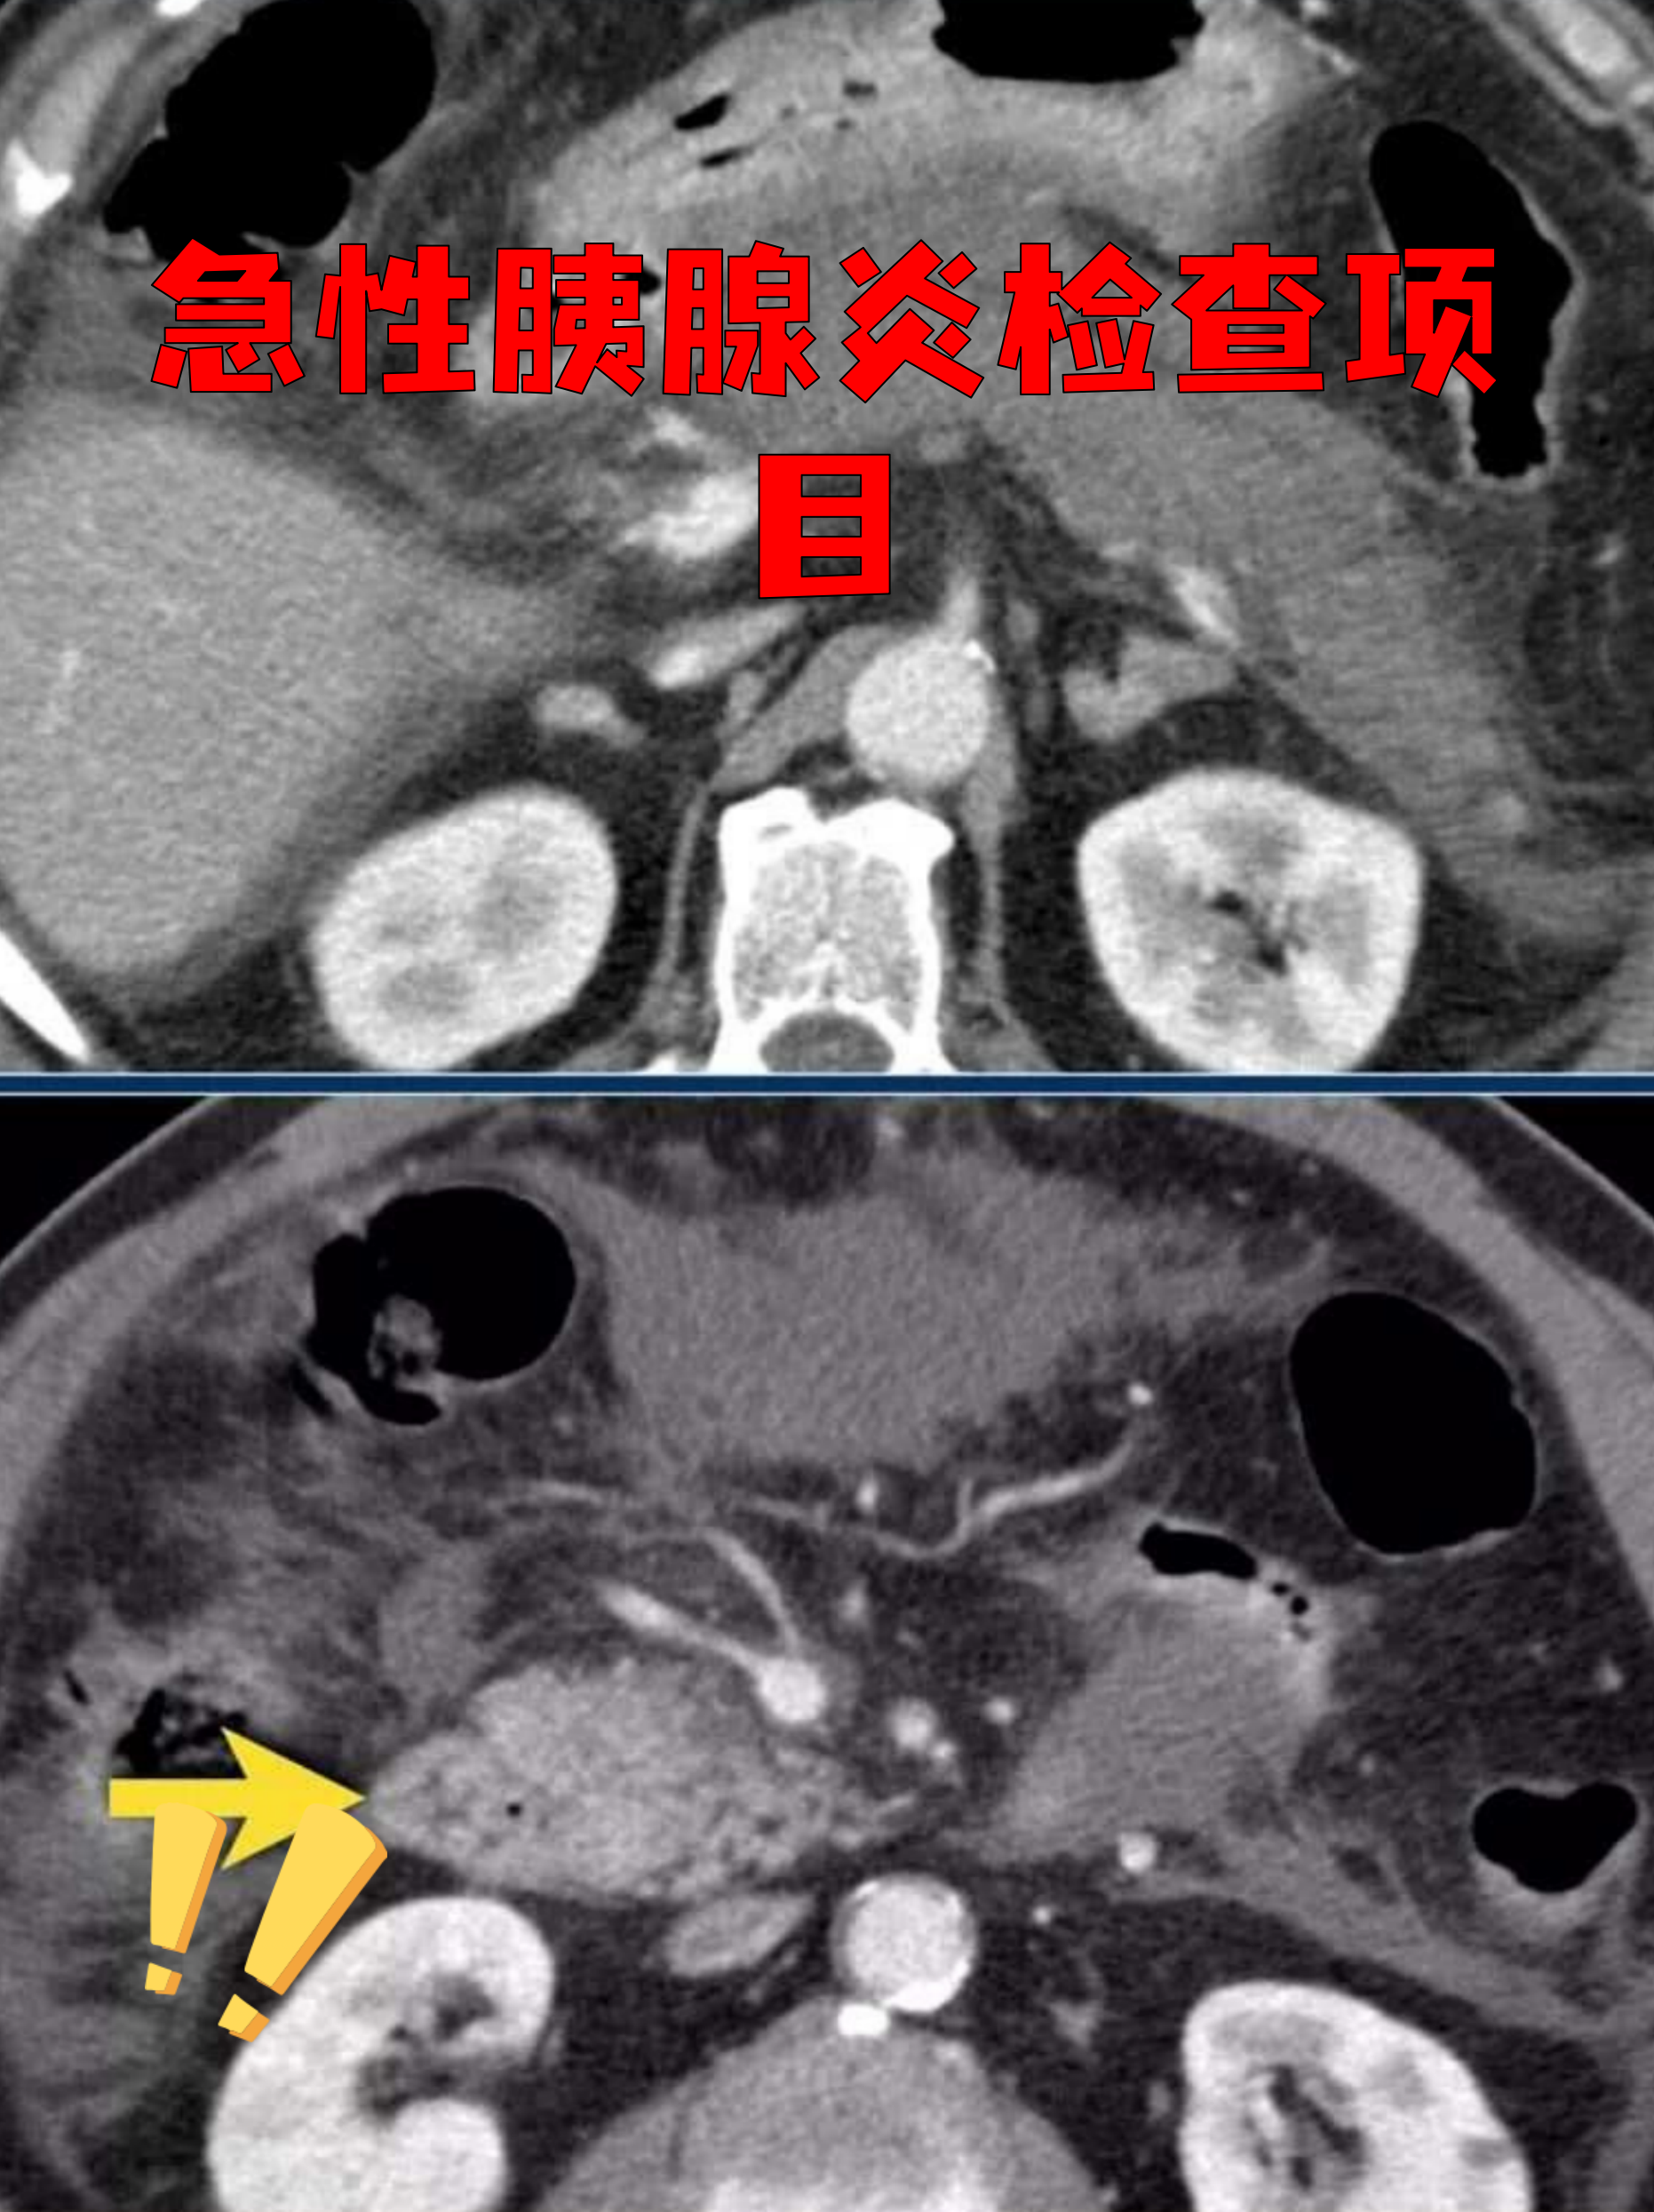

胰腺炎的检查主要通过实验室检查影像学检查以及针对特殊人群的注意事项综合判断,具体如下一实验室检查 血清淀粉酶发病数小时后开始升高,24小时达峰,45天逐渐恢复正常若血清淀粉酶超过正常值3倍可确诊急性胰腺炎,但淀粉酶水平与病情轻重不一定相关,例如出血坏死型胰腺炎患者淀粉酶可能正常或。

胰腺炎的检查主要包括实验室检查和影像学检查两方面实验室检查中,血淀粉酶检测是关键指标胰腺炎发作时,胰腺组织受损会释放大量淀粉酶进入血液,导致血淀粉酶水平显著升高,通常在发病后212小时即可检测到异常若血淀粉酶超过正常值上限的3倍,结合临床症状,可高度怀疑胰腺炎此外,脂肪酶检测也可。

胰腺炎的检查方法 胰腺炎的诊断需结合临床表现与实验室影像学检查血液检查是核心手段,通过检测血清淀粉酶脂肪酶及C反应蛋白等指标,若其水平显著升高通常超过正常值3倍,提示胰腺炎症可能但需注意,这些指标在其他疾病如肠梗阻消化性溃疡穿孔中也可能升高,需结合症状综合判断尿液检查通过测定尿淀粉酶与肌酐比值辅。